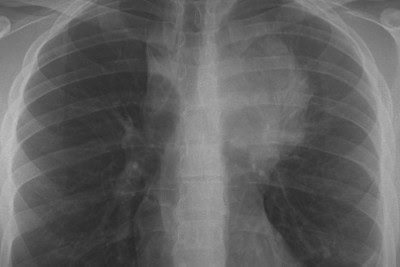

A 21-year-old male with no significant past medical history presents to urgent care with a 3-week history of progressive cough, night sweats, dyspnea, and chest discomfort. He denies sore throat, rhinorrhea, sinus congestion, hemoptysis, weight loss, wheezing, tobacco use, or illicit drug use. On examination, vital signs are within normal limits. The patient appears well and not in acute distress. Lung auscultation was clear bilaterally, and the remainder of the initial physical exam is unremarkable. …